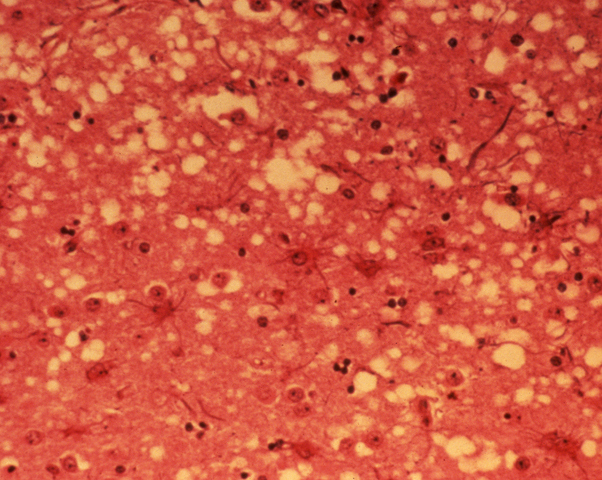

• Encefalopatía

Encefalopatía

Espongiforme bovina “vacas locas” Creutzfeldt-Jakob.